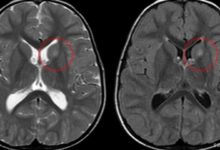

Beyin omurilik sıvısını (BOS) toplamak için bir spinal musluk (lomber ponksiyon) da yapılabilir. Beyin omurilik sıvısındaki dopamin ve serotonin seviyeleri, AADC eksikliğini teşhis etmeye yardımcı olabilir.

DDC genindeki mutasyonları tespit etmek ve teşhisi doğrulamak için genetik testler de yapılabilir.